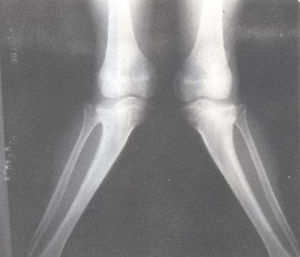

膝外翻畸形X線表現膝外翻系膝關節向外翻轉,股骨關節面向外傾斜。兒童足部縱弓尚不健全,足弓平坦,輕度外翻。在2~6歲期間的兒童存在發育性膝外翻,有輕至中度的外翻是正常的生理現象。如果膝外翻明顯,兒童走路笨拙,走路時雙膝摩擦(膝外翻又稱碰膝症),兩足分開。病兒可能使一側下肢沿另一側下肢擺動,以防膝部碰撞。病兒易疲勞,其足尖向內側偏,以使身體重心落在足底中央,即第二跖骨。如果小腿三頭肌和髂脛束攣縮,其足尖則偏向外側,常常出現小腿後側或大腿前部疼痛。嚴重膝外翻,股四頭肌力線排列紊亂,髕骨向外側滑脫。膝外翻兒童體育活動較少,身體往往肥胖。異常的負重關係能使膝內側副韌帶拉長,有時導致退行性關節炎。膝部外側受力大,股骨關節面向外傾斜。

外形特點可直接明確,下肢全長Х線片可確定外翻畸形的角度及程度。